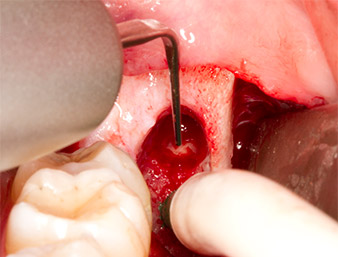

The tissue above the root remnant was not completely ossified and consisted for the most part of granulation tissue modified by inflammation (Fig.4).

To obtain autogenous material for subsequent wound treatment, healthy bone chips were harvested from the surroundings of the root remnant with a piezo surgical instrument (Piezomed B5) (Fig. 5).

The autogenous tissue was removed with the scraper-shaped section of the working part of the instrument and stored in a physiological saline solution until further use (cf. Fig. 13).